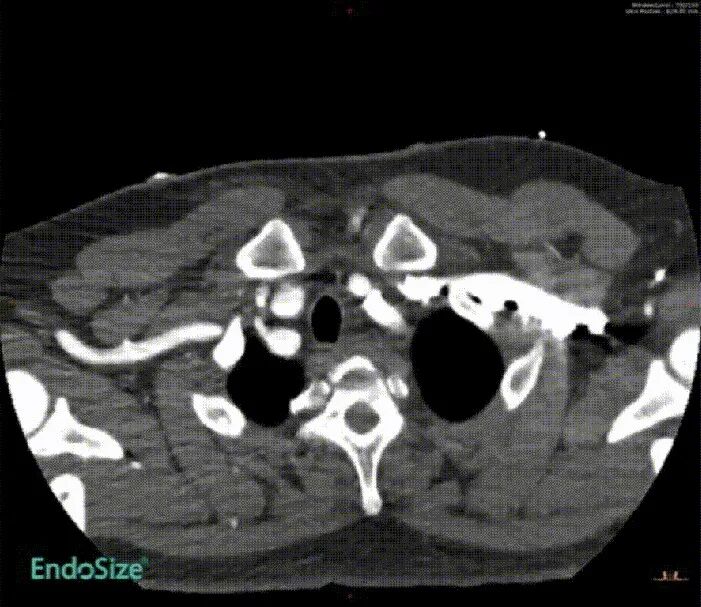

术后12个月CT血管造影(CTA)随访显示,支架移植物位置稳定,无明显移位或变形,分支血管通畅。

First-In-HuMan study--CTA

CTA preoperation

CTA 12 monthes FU